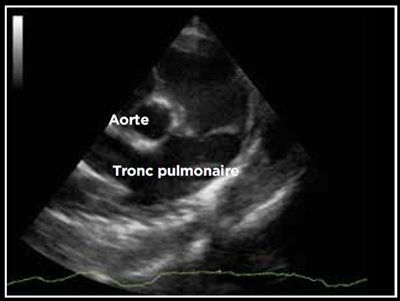

Photo 12 - Dilatation du tronc pulmonaire. Coupe transaortique abord parasternal droit. TP/Ao > 1.

Quatre types de canals sont décrits détaillant ces différentes conséquences (Tableau 1). En particulier, peuvent être présents des dilatations cavitaires (Photos 9 et 10), une insuffisance mitrale (Photo 11), une dilatation du tronc pulmonaire lors d’hypertension artérielle pulmonaire (Photo 12) [2,4].